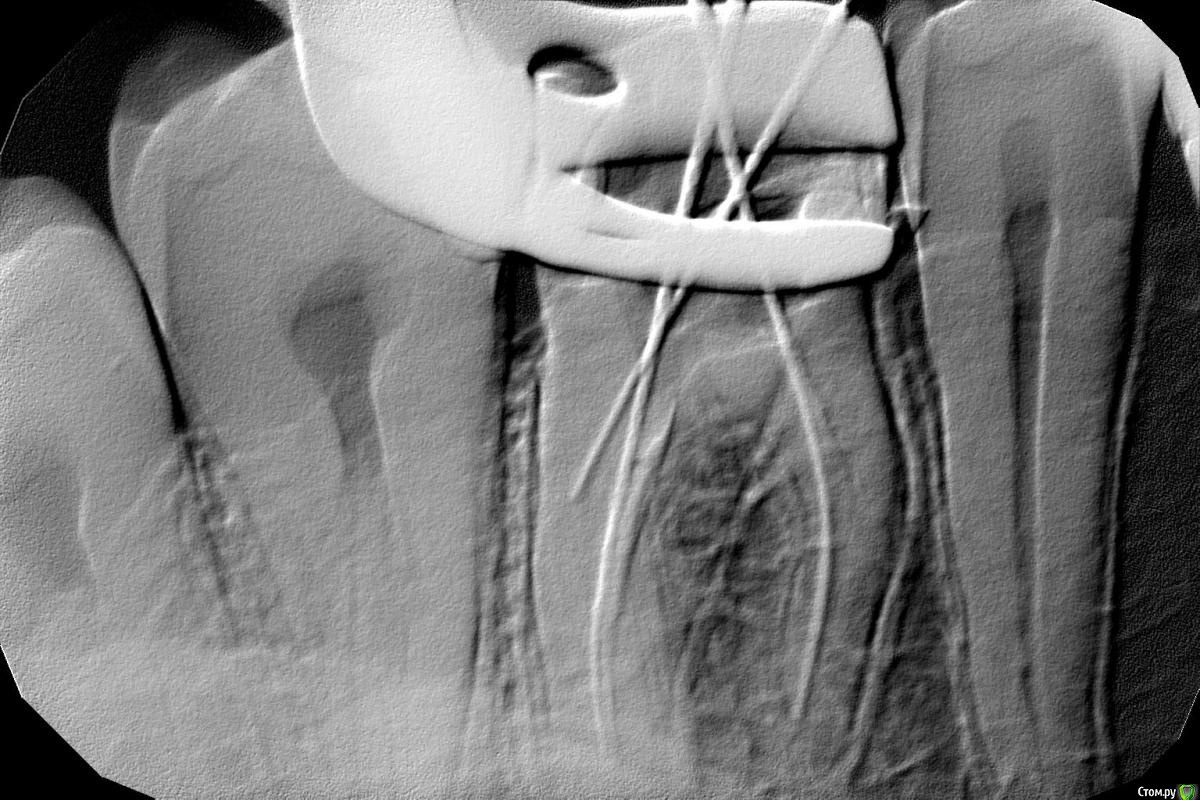

Banana Опубликовано 18 августа, 2016 Поделиться Опубликовано 18 августа, 2016 (изменено) Всем здоровья! Впервые столкнулся со стоматологическими проблемами на таком серьёзном уровне, и хотелось бы услышать мнение специалистов по поводу состояния моего зуба и того, что мне предстоит.Итак, проблема с верхней шестёркой. Анамнез. Давным-давно возник кариес, дорос до пульпита. Давным-давно обратился в государственную поликлинику. Там кариес вычистили, удалили нерв, в ходе прохождения одного из каналов допустили перфорацию, залили резорцином, сверху поставили уродливую и не функциональную светозатвердевающую пломбу. С ней я жил не тужил годы, пока не обратился за чисткой зубов в одну коммерческую клинику. Там настояли, чтобы я дал им снять пломбу, и показали, какая кошмарная чернота была под ней. Почистили, полечили. Тогда же стали проходить каналы, но прошли только три из четырёх, потому что перфорация и резорцин. К тому моменту от зуба выше десны оставались только две стеночки, и они предложили два варианта: коронка, но без всяких гарантий, что она хоть сколько-то простоит, и удаление -> синус-лифтинг -> имплантация. Про синус-лифнтинг уклончиво сказали, что по данным не ясно, понадобится ли он, и это будет видно только в ходе операции имплантации 8-мм импланта. Я выбрал последнее, поскольку это более долговечное решение проблемы. Финансовый план лечения такой:1.1 Анестезия аппликационная1.2 Анестезия инфильтрационная, проводниковая1.3 Удаление зуба сложное1.4. Закрытый синус-лифтинг (включая Bio-oss 0,25, PRP и забор материала для него)1.5. Имплантация CSM, установка формирователя десны2.1 Индивидуальная ложка2.2 Двухслойный слепок с одной челюсти (силиконовая маска)3.1 Коронка с трансокклюзией на имплант На снимках зуб до лечения и после того, как прошли три канала. На rghost выложил КТ (пароль Banana): http://rgho.st/private/8fXPD8WRy/698183a50e52bbba6e608a26d74e9344 Вопросы достопочтенной аудитории:1. Обосновано ли в данном случае удаление зуба?2. Насколько обоснован закрытый синус-лифтинг?3. Достаточно ли кости для того, чтобы провести имплантацию сразу после удаления, как и запланировано?4. К чему мне готовиться? Насколько всё плохо выглядит по снимкам? Правда ли, что после операции придётся на время исключить твёрдую пищу?5. Буду ли я играть на пианино? Всем добра! Изменено 18 августа, 2016 пользователем Banana Ссылка на комментарий